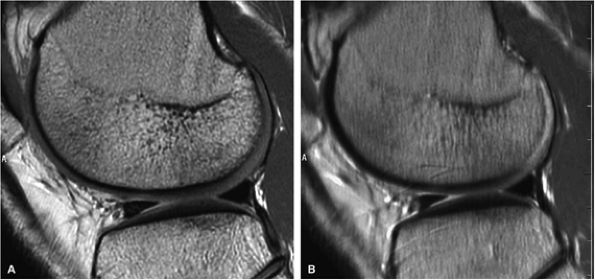

FIGURE 1.32 ● Sagittal proton density-weighted images of the knee acquired with identical parameters at 3 T and 1.5 T. Note the improved SNR of the 3 T image (A) versus the 1.5-T image (B).